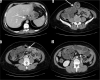

Purpose: The aim of study is to identify the frequency of acute complications and imaging findings at gastro-intestinal transit (GI) and computerised tomography (CT) in a group of obese patients who developed clinical suspicion of acute complications (painful and meteoric abdomen, nausea, vomiting, fever, intestinal blockage) in post bariatric surgery.

Material and methods: We retrospectively review 954 obese patients who underwent bariatric surgery between 2013 and 2019. The study included 72 patients who developed clinical suspicion of acute complications (painful and meteoric abdomen, nausea, vomiting, fever, intestinal blockage) within 6 days of bariatric surgery of sleeve gastrectomy, gastric banding, gastric bypass with Roux loop confirmed by CT, and who underwent a gastrointestinal transit before the CT examination.

Results: GI exam allowed visualisation of 58% of complications. Analysing the data for each surgical technique, 46 post-operative complications were found involve gastric banding. The most frequent was bandage migration (26 cases, 56 %), identified in all cases at GI transit and then confirmed on CT.

Conclusions: The study suggests that CT should be used to clarify all doubtful or clinically discordant GI transit exam results. The participation of a radiologist in qualification and post-operative evaluation is important for bariatric surgery patients.